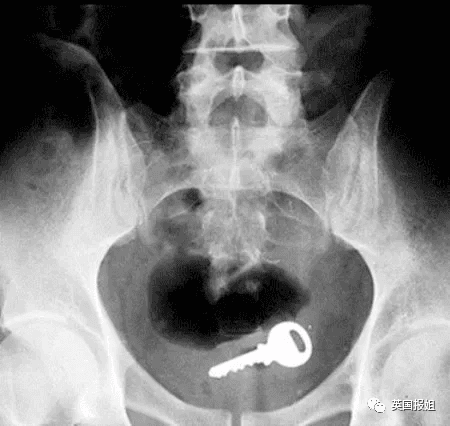

比如一把家门钥匙: